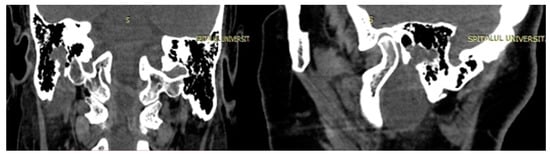

4. Imagery in Extracranial FNSs